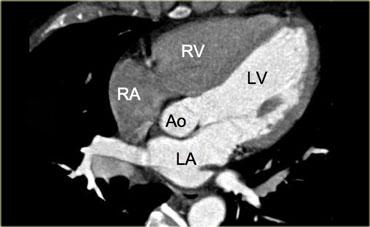

Mặt cắt 5 buồng

Hình bên trái là mặt cắt 5 buồng, tương tự như mặt cắt 4 buồng nhưng hiển thị thêm van động mạch chủ và đường ra thất trái.

Mặt cắt này đạt được bằng cách xoay mặt cắt 4 buồng lên phía đầu (cranial) thêm một chút.